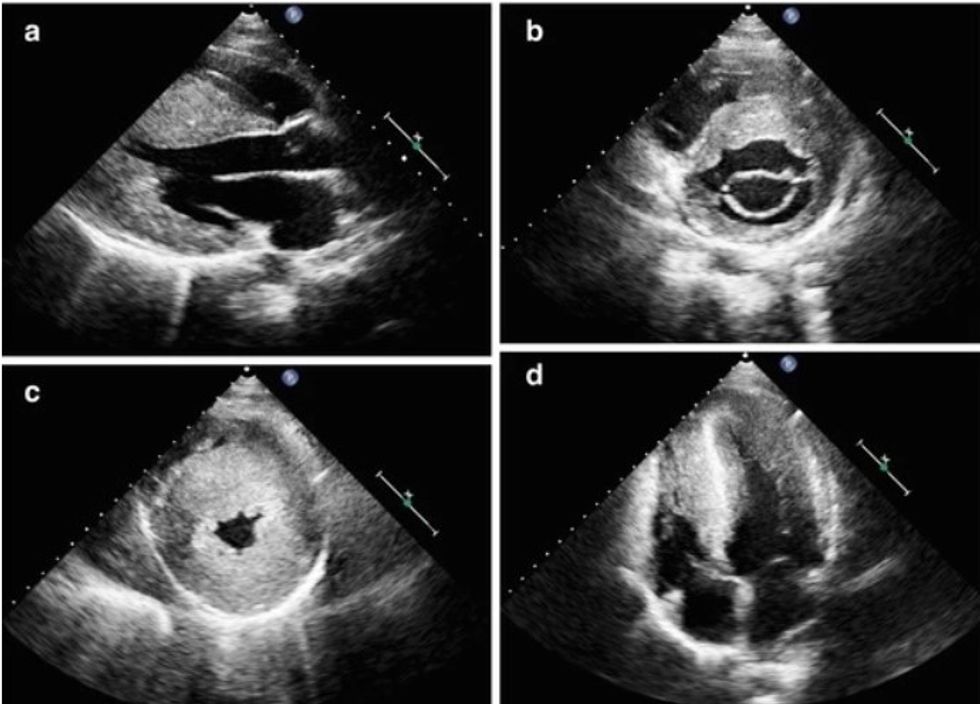

Për diagnostikimin e kësaj gjendjeje kryesisht përdoret elektrokardiografia (EKG) dhe ekokardiografia, e cila në fakt është metoda kryesore (më e zakonshme) diagnostike përmes së cilës vërtetohet sëmundja. Gjithashtu, merret parasysh aplikimi i monitorimit 24-48 orësh të ritmit të zemrës Holter, ekokardiografisë së stresit dhe rezonancës magnetike të zemrës.